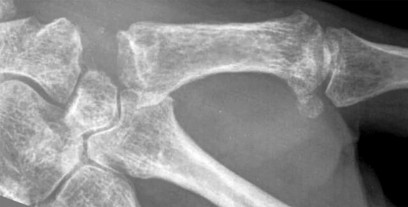

- الأشعة السينية (X-rays): هي الخطوة الأولى في تقييم الكسور، الخلوع، وتغيرات التهاب المفاصل. تساعد في تحديد مدى تدهور العظام والمسافات المفصلية. على سبيل المثال، تُظهر صور الأشعة السينية كسور السلاميات

أو كسور قاعدة العظم المشطي الخامس

، بالإضافة إلى علامات مثل "الدمعة الشعاعية" (Radiographic Teardrop) في الرسغ التي تمثل الزاوية الزندية الراحية الحرجة للكعبرة البعيدة

. - الأشعة المقطعية (CT Scan): توفر صوراً تفصيلية ثلاثية الأبعاد للعظام، وهي مفيدة جداً لتقييم الكسور المعقدة، مثل كسور العظم الخطافي (Hamate Hook Fracture) التي قد لا تظهر في الأشعة السينية العادية

، أو لتقييم مدى تدهور العظم في حالات مثل مرض كينبوك. - التصوير بالرنين المغناطيسي (MRI): ممتاز لتقييم الأنسجة الرخوة مثل الأربطة، الأوتار، الأعصاب، والعضلات. يكشف عن التمزقات،